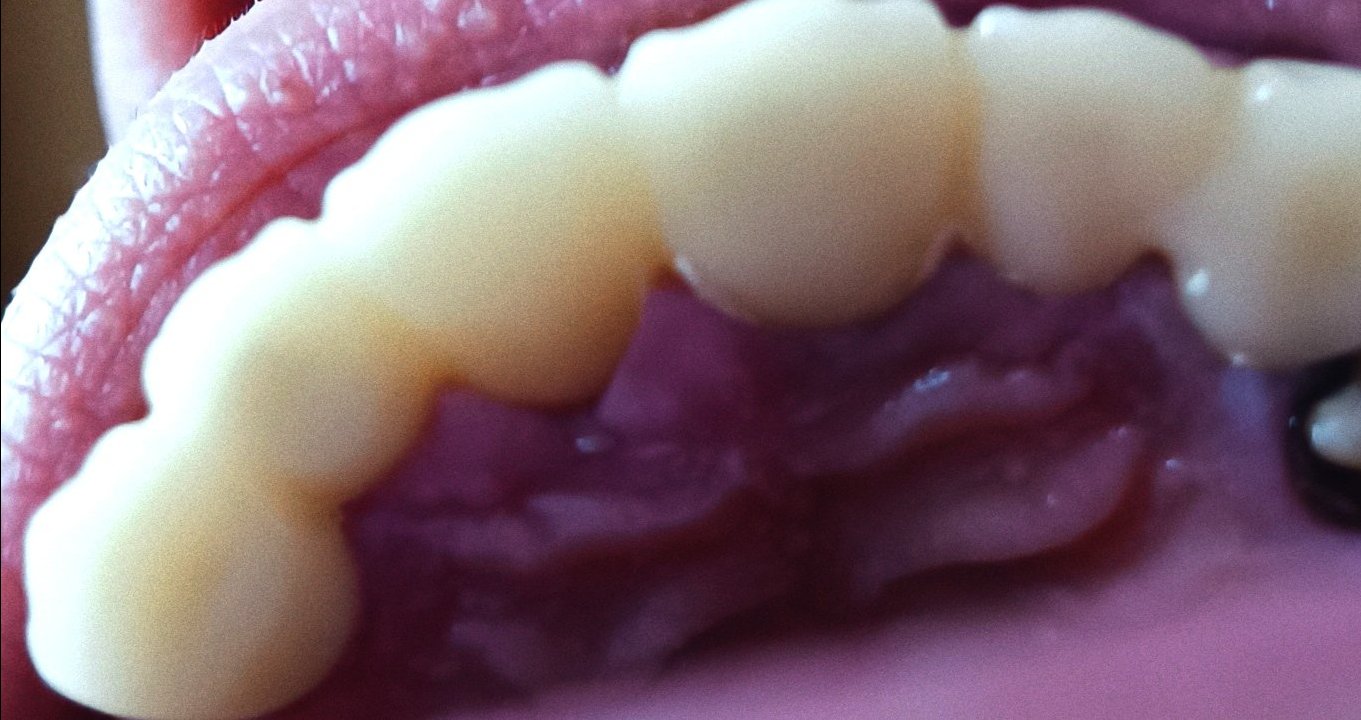

Какво може да причини постоянна болка след екстракция на нерв на зъб?

Постоянната болка след екстракция на нерв на зъб може да бъде причинена от неправилно лечение, неправилно кореново запълване или възпаление на кореновите канали. Обикновено болката трябва да намалее в рамките на 2-3 дни след процедурата. Ако болката продължава, препоръчително е да се консултирате със зъболекар.